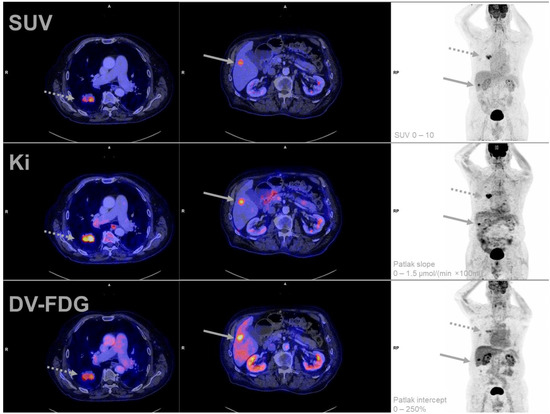

![Diagnostic Performance of Dynamic Whole-Body Patlak [18F]FDG-PET/CT in ...](https://www.mdpi.com/jcm/jcm-12-03942/article_deploy/html/images/jcm-12-03942-g002-550.jpg)